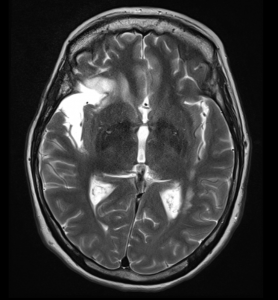

Η ασθενής παρουσίασε άμεση βελτίωση της όρασής της. Ο απεικονιστικός έλεγχος με μαγνητική τομογραφία 6 μήνες μετά την επέμβαση ανέδειξε σημαντική μείωση της κύστης και της πίεσης επί του υγιούς εγκεφάλου.

Το αποτέλεσμα 6 μήνες μετά είναι εξαιρετικό, τόσο σ’ ότι αφορά στη μαγνητική τομογραφία όσο και σ’ ότι αφορά στα συμπτώματα της ασθενούς.